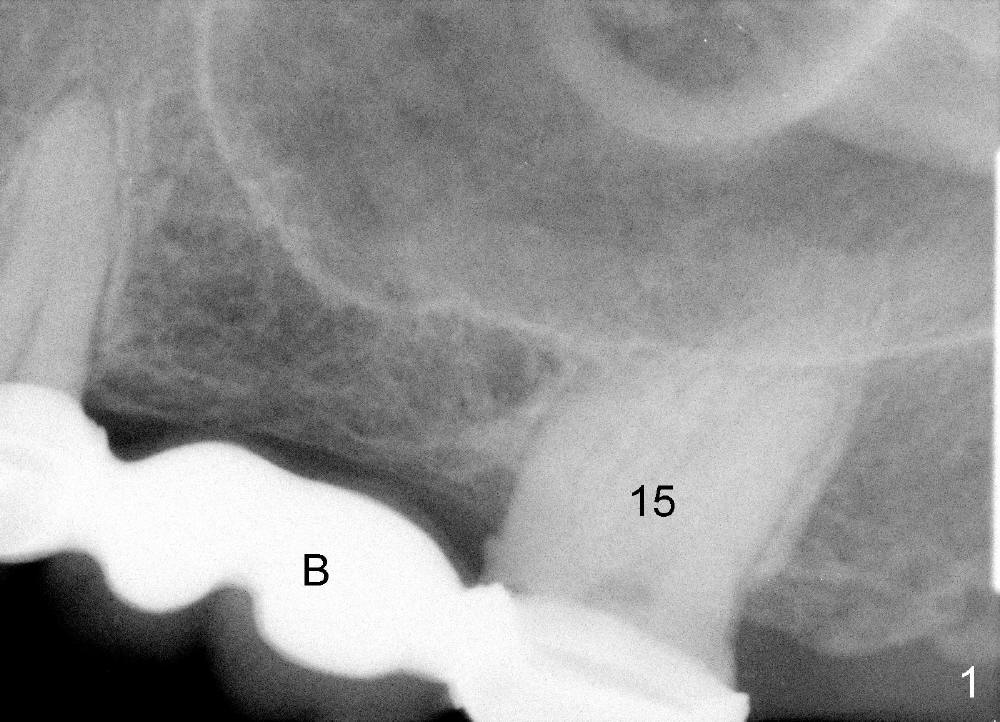

A 54-year-old lady has severe toothache in the upper left region. Exam reveals a posterior 4-unit bridge (Fig.1 B); one of the abutments (#15) needs root canal therapy (RCT, Fig.2). The bridge is temporarily recemented after RCT. Two implants are planned (4x14 mm and 5x11 mm at the sites of #13 and 14) with sinus lift/graft (Fig.3).

Make 2 surgical stents before surgery, one for surgery, the other for the 4-unit provisional bridge. Place short abutments following implantation. Occlusion of the bridge should be light.